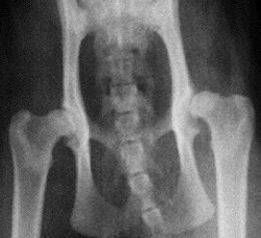

Hip Dysplasia:

Hip Dysplasia literally means an abnormality in the development of the hip joint. It is characterized by a shallow acetabulum (the "cup" of the hip joint) and changes in the shape of the femoral head (the "ball" of the hip joint). These changes may occur due to excessive laxity in the hip joint. Hip dysplasia can exist with or without clinical signs. When dogs exhibit clinical signs of this problem they usually are lame on one or both rear limbs.

Severe arthritis can develop as a result of the malformation of the hip joint and this results in pain as the disease progresses. Many young dogs exhibit pain during or shortly after the growth period, often before arthritic changes appear to be present. It is not unusual for this pain to seem to disappear for several years and then to return when arthritic changes become obvious. Dogs with hip dysplasia appear to be born with normal hips and then develop the disease later. This has led to a lot of speculation as to the contributing factors which may be involved with this disease. This is an inherited condition, but not all dogs with the genetic tendency will develop clinical signs and the degree of hip dysplasia which develops does not always seem to correlate well with expectations based on the parent's condition. Multiple genetic factors are involved and environmental factors also play a role in determining the degree of hip dysplasia.

Dogs with no genetic predisposition do not develop hip dysplasia. X-ray confirmation of the presence of hip dysplasia is available and I have my dogs' hips x-rayed when they are two years old and have the x-rays sent to Orthopedic Foundation for Animals (OFA) for evaluation. You can check their site and see the results of dogs that have passed their hip x-rays.